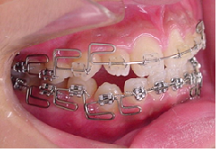

治療は上顎から矯正装置を装着していきます。

その後下顎の矯正装置を装着します。

この過程で歯並びが整いMEAW(マルチループ)を装着しやすくなります。

MEAW(マルチループ)を使用する事で上顎前突(出っ歯)や咬合高径(咬み合わせの高さ)の改善をしています。

☆治療途中

MEAW(マルチループ)を使用する事で上顎前突(出っ歯)や咬合高径(咬み合わせの高さ)を改善して2年6ヶ月で非抜歯での治療で綺麗な歯並びになりました。